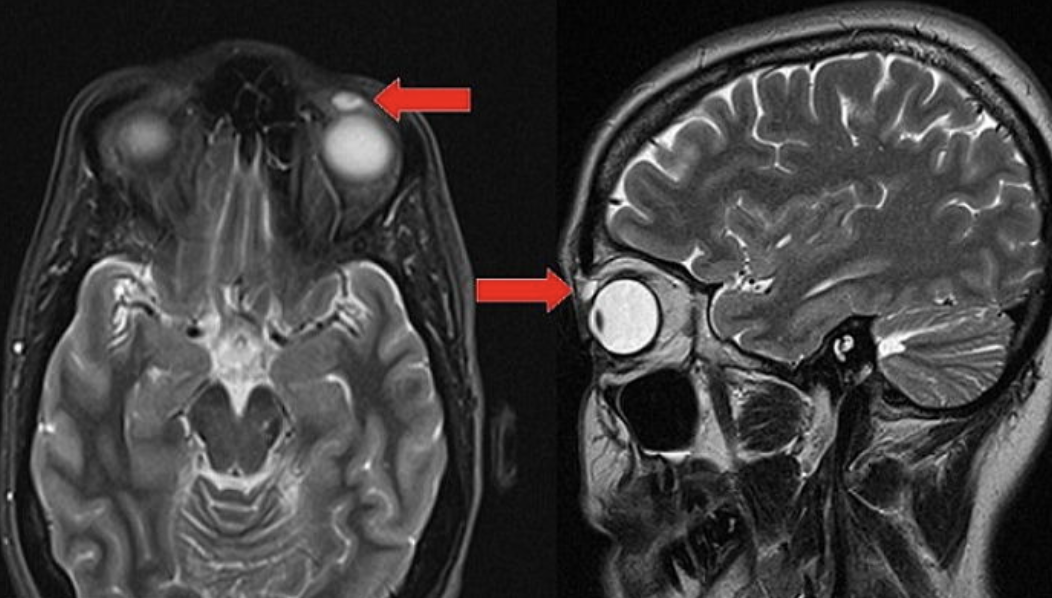

A 씨는 최근 자신의 눈꺼풀에서 볼록한 무언가를 만졌습니다. 그녀는 곧바로 병원을 찾았는데요. 의사는 낭종으로 추정했습니다.

의사는 수술을 진행했습니다. 그 결과, A 씨의 눈꺼풀 안쪽에서 오래된 콘택트 렌즈가 발견됐습니다.

무려 28년 전, A 씨는 배드민턴 경기 도중 셔틀콕을 얼굴에 맞았습니다. 그 순간 렌즈를 분실했었는데요. 그 렌즈가 밖으로 나간 것이 아니라 눈꺼풀 안쪽에 붙어있었던 것.

다행히도 렌즈는 여성의 시력에 악영향을 끼치지 않았습니다. 해당 사연은 콘택트렌즈가 눈꺼풀 속에서 가장 오래 남아있었던 사례로 의학 저널에 실렸습니다.